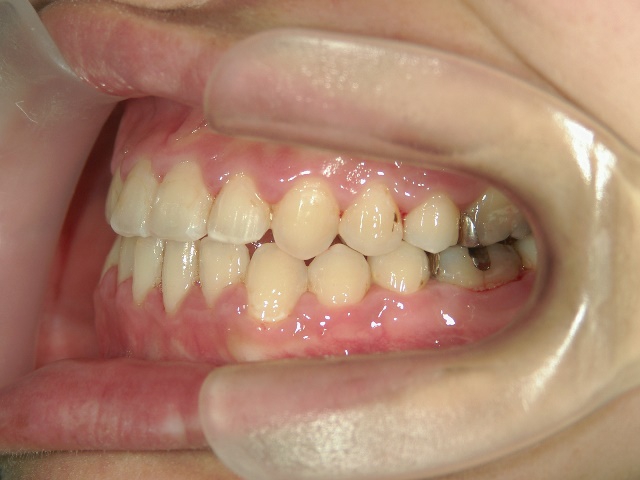

矯正歯科 治療前 急速拡大装置で上顎を広げた後、ワイヤーへ移行 非抜歯

no.31_7964_治療前_右 .JPGno.31_7964_治療前_正面 .JPGno.31_7964_治療前_左 .JPG